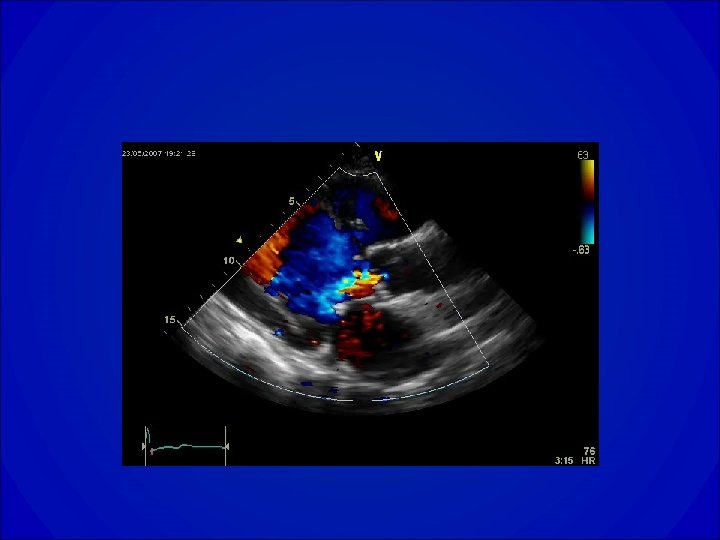

Insuffisance mitrale • Conséquence de la perte d’étanchéité de l’orifice mitral, elle se caractérise par un reflux anormal de sang du ventricule gauche dans l’oreillette gauche pendant la systole. • Valvulopathie actuellement la plus fréquente après la sténose aortique.

Examen clinique • Palpation – Choc de pointe en place ou dévié en bas et en dehors en cas de dilatation VG. – Parfois frémissement systolique. • Auscultation – Souffle holosystolique, apexien, en jet de vapeur, ne se renforçant pas après les diastoles longues. – Irradie classiquement dans l’aisselle, mais dans les atteintes de la petite valve a une irradiation ascendante vers la base. – En cas de fuite volumineuse : B 3 roulant, EB 2 au foyer pulmonaire témoignant d’une HTAP.

Diagnostic • ECG ACFA, Surcharge auriculaire gauche, Signes d’atteintes VG (HVG, Ondes Q…. ) • Radiographie de thorax= dilatation du VG • ETT +/- ETO -Confirmation et quantification de la fuite -Faisabilité d’une réparation chirurgicale (plastie) -Évaluation du retentissement VG -Lésions associées ?

Indications opératoires dans l’insuffisance mitrale • • • Patients symptomatiques. FEVG < 60% DTS VG > 45 mm Fibrillation auriculaire. HTAP > 50 mm. Hg au repos ou > 60 mm. Hg à l’effort. • IM volumineuse et forte probabilité de pouvoir réaliser un geste conservateur: influence des lésions, de l’expérience de l’équipe chirurgicale et de l’âge.